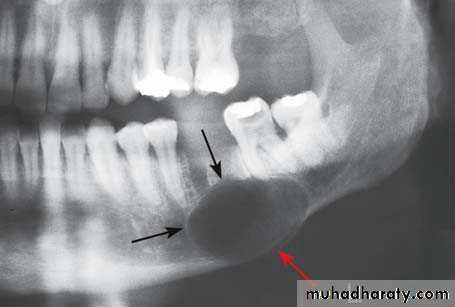

Radiographic interpretation

Intraoral apical films usually suffice for small cysts.

Larger ones may need extraoral and occlusal views of the jaws to show their full extent.

this is demonstrated by radiographs taken in two planes, as treatment planning depends on a clear understanding of their size and their relationship to those vital structures on which they may encroach.

Cysts appear as rounded, radiolucent areas

Sharply demarcated from normal bone by a thin, radiopaque limiting line of compact bone, this line is not usually present on radiographs of apical granuloma and is often absent or hazy round in infected cysts